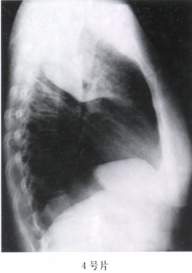

4.(4号片)

A、右上肺不张

B、右中心性肺癌

C、右上肺结核

D、右周围性肺癌

E、右上肺大叶性肺炎

答案:1—6:EDACAC 15—20:ACBDED